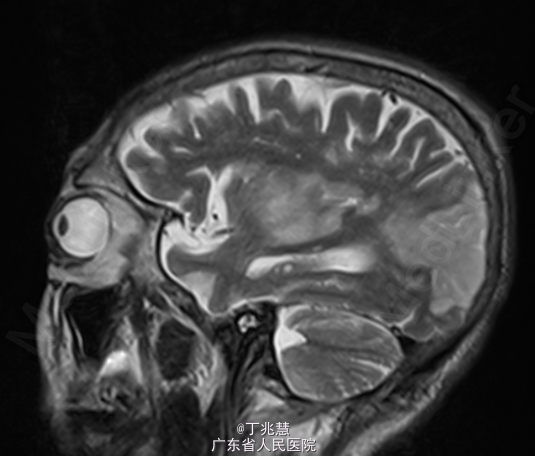

女性,46岁。因“反复发热、头痛2月”入院。患者自2个月前无明显诱因出现头痛,呈持续性,起病初期头痛程度轻,可忍受,自服药治疗(具体用药不详)病情未见好转,且头痛程度逐步加重,难以忍受,无恶心,呕吐,无肢体抽搐,间中有发热,体温最高可达39.2摄氏度。 既往糖尿病史5年,控制不佳。

查体:心肺腹查体未见异常。神经专科:右侧上下肢肌力0级左侧上下肢体肌力5级。 颈强直,颏胸距4横指,双侧Kernig征(+)。

诊断:结核性脑膜脑炎; 治疗:抗结核治疗。

随访:患者转胸科医院进一步治疗,具体不详; 讨论:结核菌一般侵犯脑膜多见,较少累及大脑实质,本例患者累及脑实质,有肢体无力表现。经规律抗结核治疗后预后相对良好。